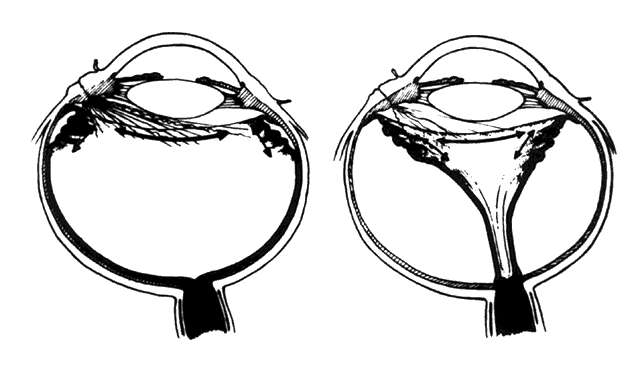

hemorrhage, retinal breaks, and retinal detachment. SUBLUXATION OR DISLOCATION OF THE LENS Minor degrees of subluxation should be suspected when phakodonesis or iridodonesis is noted. Zonular rupture is certain if there is vitreous prolapse into the anterior chamber. In the absence of cataractous changes and related visual impairment, treatment is not indicated. A subluxated, cataractous lens can be removed by aspiration-irrigation or phacofragmentation through a limbal incision, but complications may occur, including posterior dislocation of the lens or lens fragments, vitreous prolapse and incarceration, and vitreous aspiration with resultant vitreous base traction and retinal tear formation. Also, visualization of the anterior vitreous by coaxial illumination is poor compared with fiberoptic endoillumination. These problems make pars plana lensectomy an attractive alternative. Bimanual techniques permit fixation and simultaneous removal of the lens by the vitreous suction-cutter, if the lens is soft, or phacofragmentation if it is sclerotic (Fig. 1A). Posteriorly dislocated fragments can be removed safely, with minimal vitreous traction, using the same incisions and instruments (see Fig. 1B). With endoillumination, prolapsed and juxtalenticular vitreous is readily identified and excised with the vitrectomy probe. Without question, pars plana lensectomy is the preferred method for removing a completely dislocated lens. The technical aspects of dislocated lens and lens fragment removal are described elsewhere in these volumes. VITREOUS HEMORRHAGE Blood in the vitreous may come from tears in the iris, ciliary body, choroid, or retina. Hemorrhage from choroidal ruptures accumulates beneath the neurosensory retina; it then passes through the retina into the vitreous without necessarily causing a retinal break. Regardless, it is important to assume that a retinal break is present until proved otherwise. Vitrectomy is indicated for vitreous hemorrhage caused by ocular contusion when a retinal detachment is suspected because of sudden additional loss of vision, when a retinal detachment is detected through a window in the hemorrhage, when a large retinal break or retinal detachment is diagnosed by ultrasound, or when there is no improvement after a reasonable period of observation. Preoperative contact A-scan and B-scan ultrasonography is helpful for detecting posterior vitreous detachment and differentiating it from retinal detachment. It is dangerous, however, to rely completely upon the accuracy of ultrasound. The presumed posterior hyaloid should be approached with caution until it can be identified with certainty. A standard three-port vitrectomy technique is preferred for nonclearing vitreous hemorrhage. Initially, a central core of opaque vitreous is removed, beginning sufficiently close to the lens that the tips of the cutter and endoilluminator can be visualized. The excision is carried posteriorly, removing successive layers of hemorrhagic and fibrinous vitreous, until the anticipated plane of the posterior hyaloid is approached. A constant surveillance is maintained for a gray membrane containing radially oriented vessels (undiagnosed detached retina). A small opening is made in the detached posterior hyaloid, through which unclotted blood is aspirated by use of active suction from a soft-tipped cannula. Once the retina has been visualized, it is best to remove as much retrohyaloid blood as possible to prevent dispersion into the vitreous cavity with consequent loss of visual control. If the posterior vitreous cortex is not detached, it can be separated from the retina by gentle suction with a soft-tipped cannula at the edge of the optic disc. The elevated cortex is penetrated with a hooked needle or myringotomy blade, creating a window through which a pick is introduced to enlarge the area of cleavage. With the plane between hyaloid and retina established, the surgeon attempts to remove the entire cortical vitreous except for the firmly attached portion at the anterior vitreous base. Cortex that does not separate with gentle manipulation is isolated from surrounding vitreous to eliminate traction on the retina. It is important to remove the cortical vitreous from areas adjacent to retinal breaks. Failure to do so may result in subsequent tangential traction and retinal detachment. A scleral buckle should be considered if retinal breaks cannot be freed from surrounding vitreous cortex. The placement of sclerotomies close to the 3 o'clock and 9 o'clock positions facilitates maximal excision of the hemorrhagic anterior vitreous skirt, thereby improving visualization of the peripheral retina and pars plana. With use of coaxial illumination and scleral depression, the peripheral vitreous on the temporal side of the globe is trimmed with the cutter placed in the temporal sclerotomy, reaching both the superior and inferior quadrants, after which it is transferred to the nasal sclerotomy, and the process is repeated. The fiberoptic endoilluminator may damage the lens if used internally to illuminate the peripheral vitreous on the opposite side of the globe. However, the cone of light from the probe may be directed through the cornea to augment or replace the coaxial light source. Hemorrhagic retrolenticular vitreous can be stripped from the posterior capsule of the lens by gentle aspiration into the cutting port followed by withdrawal of the probe and simultaneous activation of the cutting mode. This technique is dangerous in young children because the retrolenticular vitreous is adherent to the lens, which is sufficiently pliable for aspiration into the port with consequent cataract formation. When the lens is clear, the process of removing peripheral and retrolenticular vitreous is less important than preserving lens integrity in most cases. It is important to expose the peripheral retina and vitreous base because most retinal breaks caused by ocular contusion are located in this area.2 All retinal breaks should be treated. Endolaser is used for posterior breaks, whereas peripheral breaks are treated with indirect laser assisted by scleral depression or transscleral cryoretinopexy. Cryotherapy is preferred when residual opaque vitreous partially obscures the targeted break. Encircling scleral buckles are not necessary after vitrectomy for nonclearing vitreous hemorrhage caused by ocular contusion when a clear view of the fundus periphery reveals no peripheral retinal tears or signs of traction, such as vitreous base avulsion. Similarly, the support of a buckle is usually not needed for treated retinal breaks without retinal detachment. A local scleral buckle should be used when there is residual traction on a posterior break. The peripheral retina should be supported by an encircling scleral buckle when traction on breaks in the oral zone persists or the periphery is poorly visualized because of residual opaque vitreous. RETINAL BREAKS Retinal breaks are created at the time of nonpenetrating blunt injuries3 in 10% to 20% of eyes.3–6 Retinal dialyses are most frequent2–6 and are most often found in the lower temporal (Fig. 2) and upper nasal periphery (Fig. 3).2 Large irregular breaks at the point of impact of blunt trauma are less common but are equally characteristic of nonpenetrating injuries (see Fig. 3).2,7,8 Horseshoe and opercular tears of the equatorial retina (see Fig. 3) are associated with the more characteristic breaks in 25% of eyes.2 Small round holes in atrophic retina at the point of traumatic impact and macular holes (see Fig. 3) are infrequently observed after ocular contusion.2,8 Prophylactic treatment of most traumatic retinal breaks is indicated. Breaks at the point of impact are one exception because they are frequently self-sealing. The surrounding necrotic retina and choroid often unite in a common scar without prophylaxis. It is wise, however, to treat these large tears when scleral depression reveals a slight elevation and movement of their edges and the surrounding retina. Traumatic macular holes also are not treated to prevent additional loss of central vision. They seldom cause retinal detachments when left alone. RETINAL DETACHMENT Although retinal breaks are produced at the time of injury, the retinal detachment may be delayed for months to years because the vitreous gel acts like a tamponade until liquefaction occurs.2 The detachment is typically shallow and slowly progressive because the large volume of vitreous gel in younger eyes prevents bullous retinal elevation as commonly seen in older patients with nontraumatic retinal detachments. Careful preoperative and intraoperative indirect ophthalmoscopy with scleral depression is the key to successful treatment of detachments caused by traumatic retinal dialyses. Small dialyses at the vitreous base borders are difficult to identify, particularly in the upper nasal quadrant where they frequently occur. Breaks of the pars plana epithelium, at the anterior vitreous base border, are less apparent than retinal tears at the posterior edge of the vitreous base. Small dialyses are closed by scleral depression, in which case they are more easily seen on the lateral slopes of the indentation than on its crest. Transscleral cryotherapy is diagnostically helpful. It is not unusual to discover breaks at the vitreous base border for the first time when the edges of the tear are whitened by freezing a suspicious area. It is prudent to treat the entire zone of vitreous base pathology with cryotherapy under direct visual control (see Fig. 3). In this way, treatment of all retinal breaks is assured. The anterior, posterior, and lateral limits of the treated zone are carefully localized and supported by a broad scleral buckle to relieve traction on the entire area. The posterior edge of the dialysis should fall on the crest of the buckle, which must be sufficiently broad to support the anterior edge as well, thereby preventing a recurrent detachment due to anterior leakage. Segments of grooved solid silicone tires are used together with an encircling band, which is positioned on a great circle of the globe to minimize anterior or posterior migration of the buckle. The band is tightened to ensure permanent indentation of the tire segment, but a high encircling buckle is avoided because it promotes posterior gaping or “fish-mouthing” of the dialysis. The band is anchored by a nonabsorbable mattress suture or scleral belt loop in each of the quadrants not occupied by the tire segment. The retinal detachment is often shallow. To avoid retinal perforation or incarceration, subretinal fluid is released through a sclerotomy in an area of sufficient retinal elevation determined by intraoperative indirect ophthalmoscopy with scleral depression. Viewed in profile, the scleral indentation helps gauge the distance between retina and retinal pigment epithelium. To avoid retinal incarceration and blowout, sclerotomies posterior to the buckle should be securely closed after the release of fluid, particularly if additional manipulation of the buckle or an intravitreal gas injection is anticipated. Retinal dialyses in the lower temporal quadrant are often very large, with gaping posterior edges located well behind the equator (see Fig. 2). They are caused by injuries impacting the lower temporal portion of the globe that result in the dissolution and disappearance of retinal tissue.8 In contrast to nontraumatic giant retinal tears with rolled-over retina, they respond favorably to scleral buckling without vitrectomy. A scleral buckle is indicated for smaller dialyses that can be closed with an explant of reasonable size. Very large breaks, as illustrated in Figure 2, are best treated with vitrectomy, gas tamponade, and laser, as recommended for nontraumatic giant retinal tears, rather than with a very large scleral buckle. Traumatic horseshoe and opercular tears are treated with scleral buckling surgery, as are similar nontraumatic retinal breaks. Likewise, traumatic macular holes in detached retina are managed by vitrectomy, internal drainage, and gas tamponade. The use of laser in such cases is controversial but is probably indicated for recurrent detachments and eyes with pre-existing poor central vision due to other traumatic macular damage. |